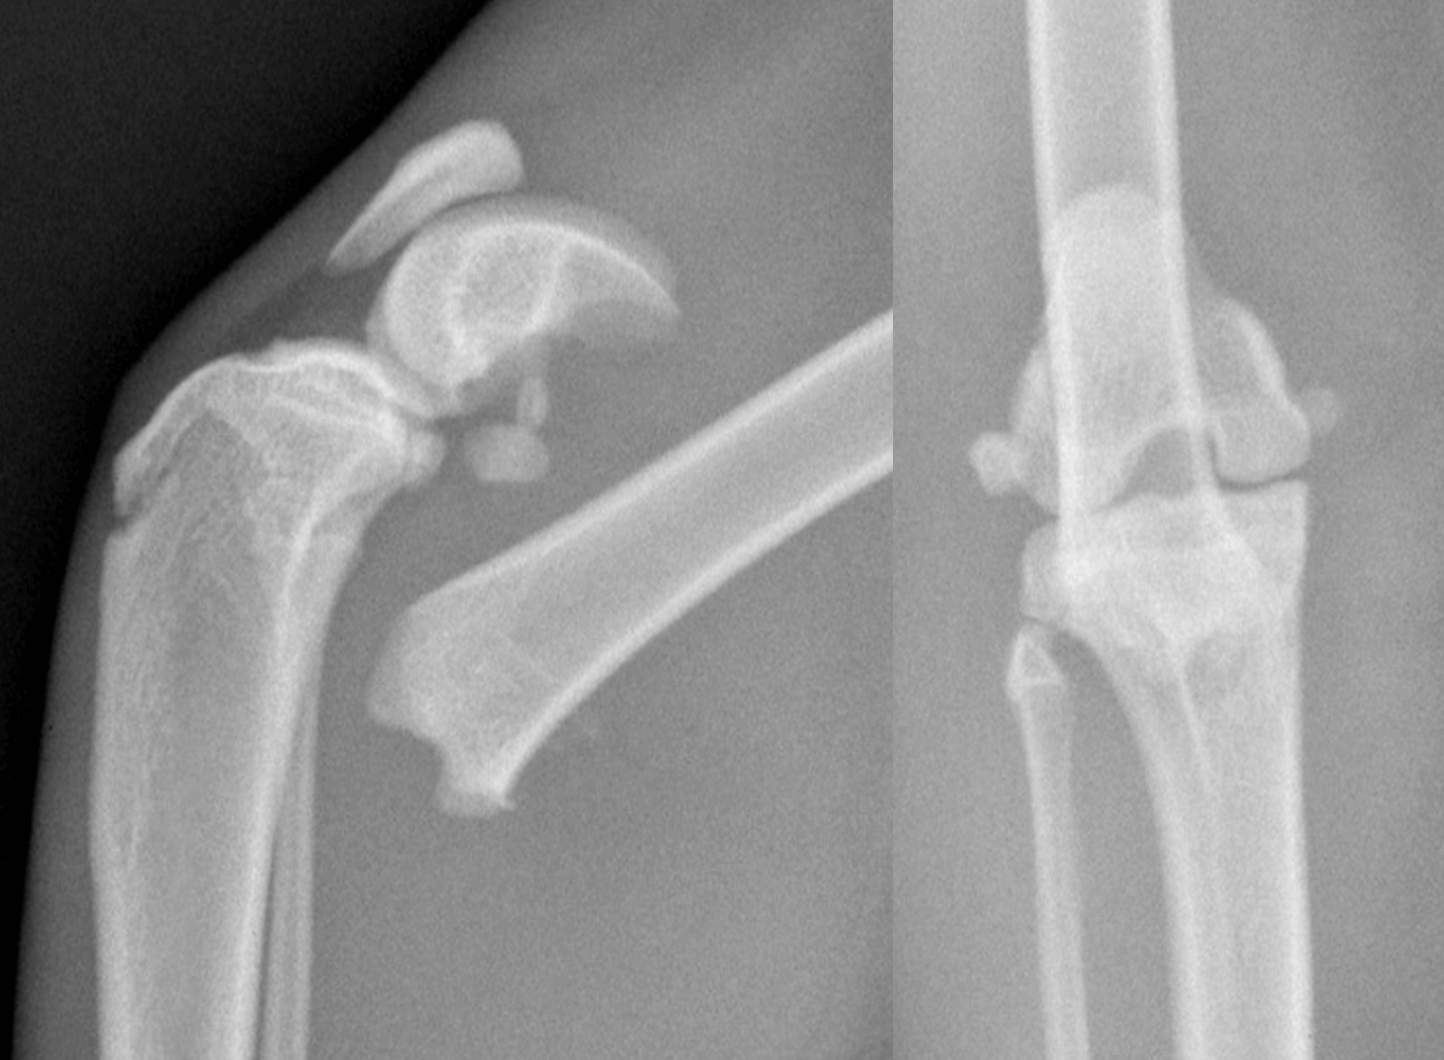

Fracture Salter Harris Type I du fémur distal chez Olaf

Fracture Salter Harris Type I du fémur distal chez Olaf (profil et face)